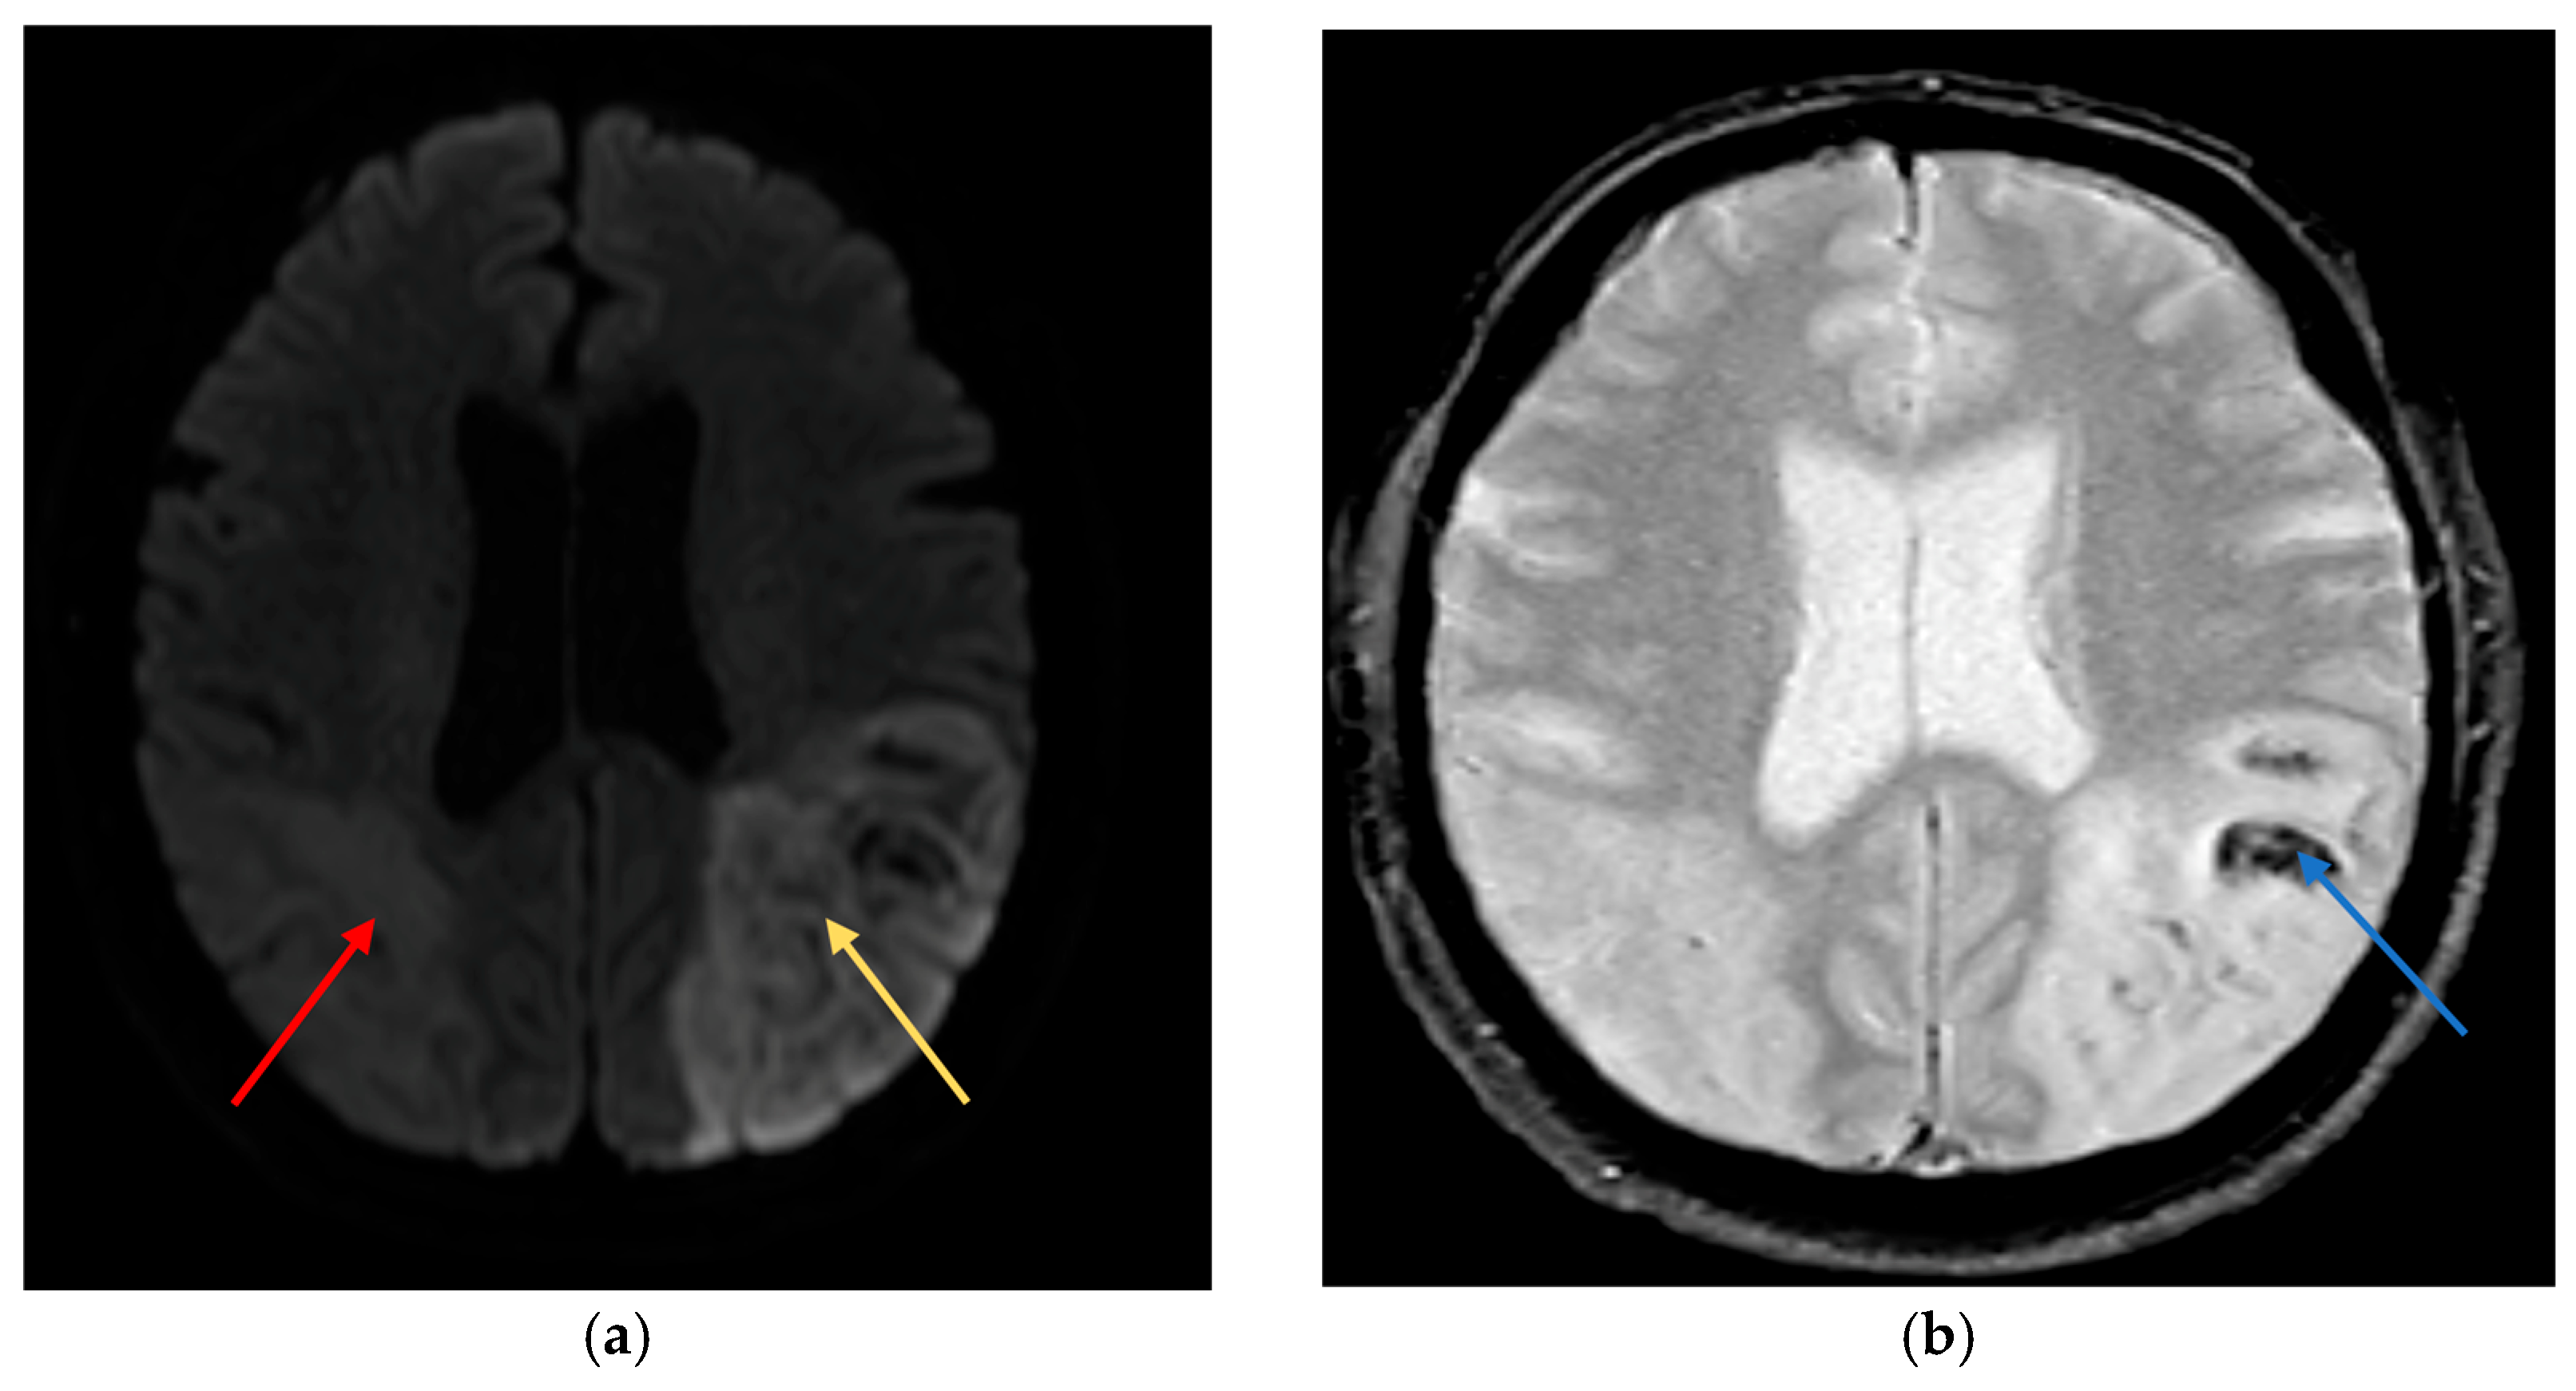

On day 2, further neurological signs evolved including cortical visual loss, persistent dysphasia, and neurocognitive impairment. By day 3, the patient demonstrated visual inattention, inability to follow two-step commands, and absent visual threat on the left. Diffusion-weighted MRI revealed a large acute infarct in the left parietal lobe and a subacute infarct in the right parietal region (Figure 2a). Fast field echo sequences indicated haemorrhagic transformation of the left-sided infarct (Figure 2b). Aspirin was discontinued, with plans for repeat imaging to guide anticoagulation restart.

Clinically, the patient presented with an atypical and rapidly evolving neurological syndrome. Initial confusion and agitation, coupled with impaired command following, likely delayed recognition of the cerebrovascular insult. Neuroimaging subsequently revealed bilateral parieto-occipital infarctions, accounting for the constellation of cognitive, sensory, and visual disturbances observed. Imaging revealed infarcts predominantly involving the left angular gyrus (Brodmann area 39) and adjacent inferior parietal lobule, regions classically associated with Gerstmann syndrome. The right parieto-occipital lesion affected the non-dominant hemisphere’s homologous areas, contributing to spatial neglect and impaired visual awareness. On diffusion-weighted MRI (Figure 2a), the infarcted regions aligned with cortical areas subserving symbolic representation and spatial mapping. Notably, the haemorrhagic transformation (Figure 2b) likely limited early re-initiation of anticoagulation, underscoring the clinical utility of sequential imaging. These anatomical correlates correspond well to the observed deficits and support a network-based model of cognitive disruption.

Figure 2. Bilateral Parietal infarcts on MRI (a) Diffusion weighted imaging (DWI) shows a large acute cortical infarct in the left parietal lobe (yellow arrow), with a subacute infarct in the right parietal lobe (red arrow), correlating with the patients cognitive and visuospatial deficits. (b) Fast field echo (FFE) sequence demonstrates haemorrhagic transformation within the left parietal infarct (blue arrow), which informed temporary anticoagulation management.